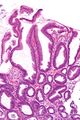

Reactive gastropathy - intermed mag.jpg

Micrograph of a reactive gastropathy. H&E stain.

Reactive gastropathy, is characterized histologically by:[2]

- Foveolar hyperplasia (black arrow), as a tortuosity in the "neck" region of the gastric glands.

- Scant or minimal inflammatory cells (white arrow), i.e. lack of large numbers of neutrophils and plasma cells..

- Smooth muscle hyperplasia in the lamina propria (in black oval).

The diagnosis is by examination of tissue, e.g. a stomach biopsy.